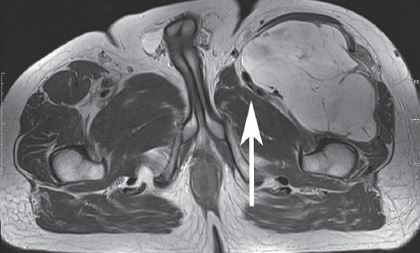

MRI of quadriceps tumor

This MRI shows a large mass on the upper left hand side of the thigh (upper right hand side of the image) which is compressing the muscles and nerves.